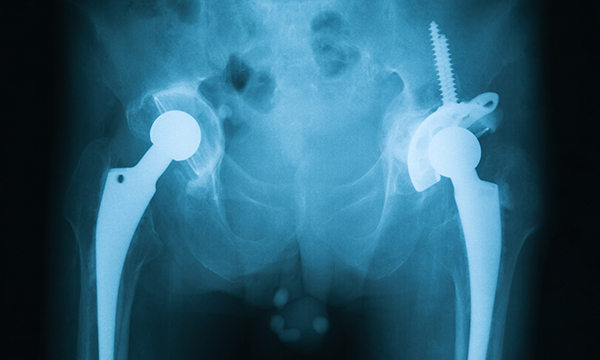

The purpose of hip replacement surgery has been called into question, after researchers from the University of East Anglia (UEA) found that patients’ physical activity does not increase following a total hip replacement